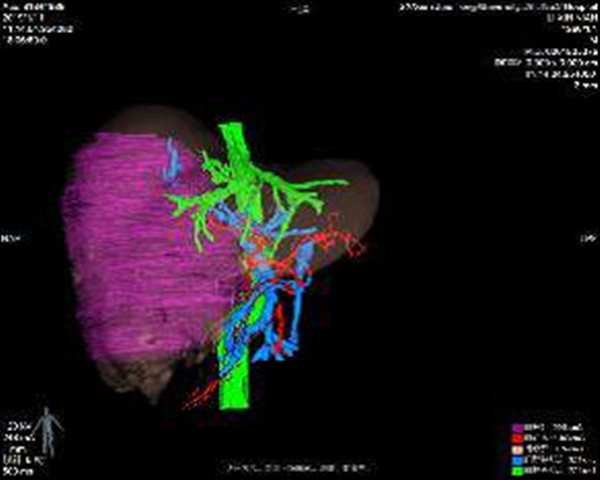

借助普外科3D辅助成像系统术前进行精准评估,实际肝体积3631ml,标准肝体积1288ml,肿瘤体积2048ml,左半肝体积(含尾状叶左半部分)1478ml,除右半肝剩余肝脏体积比标准肝体积大,说明患者左半肝已明显代偿,手术切除是可行的。术前肝功能Child-Pugh A级,ICG 15min滞留率 10.5%,无手术禁忌。